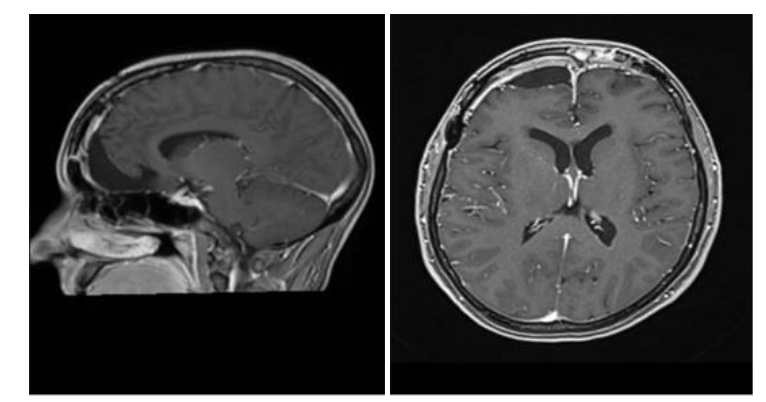

Due to these symptoms, a magnetic resonance imaging (MRI) scan of the brain was requested, which revealed a large extra-axial expansile mass with a broad dural attachment located on the floor of the anterior cranial fossa and involving the planum ethmoidale, crista galli, and olfactory groove. The mass showed a hypointense signal on both T1- and T2-weighted sequences, with intense and homogeneous enhancement after administration of gadolinium-based contrast agent. It measured approximately 5.8 × 5.0 × 4.9 cm in its largest diameters. There was compression of the anterior horns of the lateral ventricles, predominantly on the right side, in addition to a deviation of the midline structures toward the left by approximately 1.4 cm. The patient underwent a subsequent contrast-enhanced cranial MRI, which supported the diagnosis of a meningothelial lesion. Arterial and venous magnetic resonance angiography revealed a large left frontopolar vascular branch at the superior and medial margins of the lesion. Caliber asymmetry was observed between the transverse and sigmoid sinuses and cranial segments of the internal jugular veins, which were smaller on the left, probably representing hypoplasia on this side.